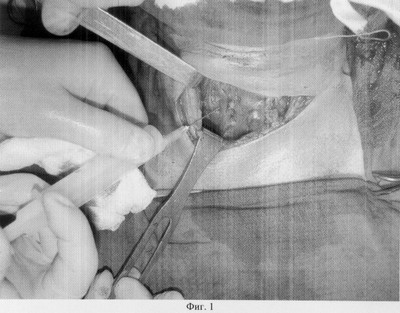

Существо изобретения иллюстрируется изображениями, где на фиг.1 показано интраоперационное введение биоматериала в остаточную ткань (культю) правой доли щитовидной железы;

Резекция обычно начинается с большей по размерам, как правило, левой доли. Мобилизация долей проводится без пересечения перешейка. Магистральные щитовидные артерии перевязываются около капсулы. Зажимы накладывают на сосуды вдоль и параллельно заднебоковой поверхности в нижней части доли и сверху по мере доступности, последовательно переходя с одной стороны доли на другую с оставлением тиреоидной ткани по заднебоковой поверхности. Аналогично зажимы накладываются и на перешеек. После мобилизации доли с полюсами производится клиновидная резекция последней. Затем накладываются несколько капроновых П-образных швов, соединяющие латеральный и медиальный края капсулы доли. Манипуляции по мобилизации, резекции и формированию культи второй доли осуществляют по той же методике. После резекции железы в толщу сформированной культи каждой доли щитовидной железы инъекционно вводят 1-2 мл комплексного аллогенного биоматериала (фиг.1), разведенного в физиологическом растворе в соотношении: 40-50 мг биоматериала на 1 мл физраствора. Затем рану послойно зашивают с оставлением дренажа.